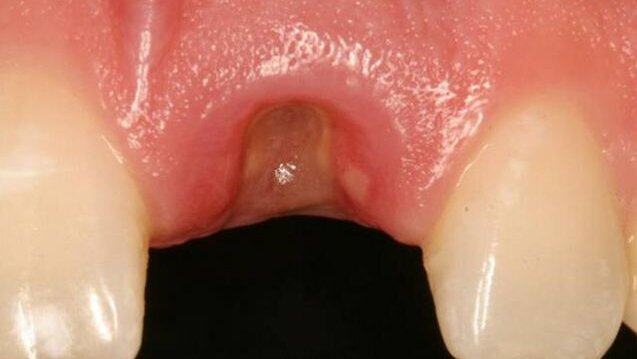

Après trois mois de guérison sans problème (fig. 4), la phase 1 de l'implantation a été lancée.

L'emplacement de la 21 a bien guéri, sans incident, après trois mois (fig. 8). Après utilisation d'une technique de tréphine de tissu, pour enlever la muqueuse, immédiatement sur l'infrastructure (fig. 9), un pilier de cicatrisation, monobloc, de 4.1 millimètres par 5 millimètres (profil d'émergence) a été placé, sur l'implant 21. (Certain EP Healing Abutment, BIOMET 3i, Palm Beach Gardens, FL, USA)